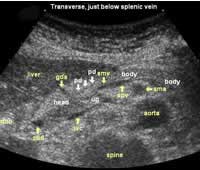

The following study describes anatomical landmarks in the ordinary pancreas of a thin patient:

Transverse planes in caudal direction:

![]() Image02 |